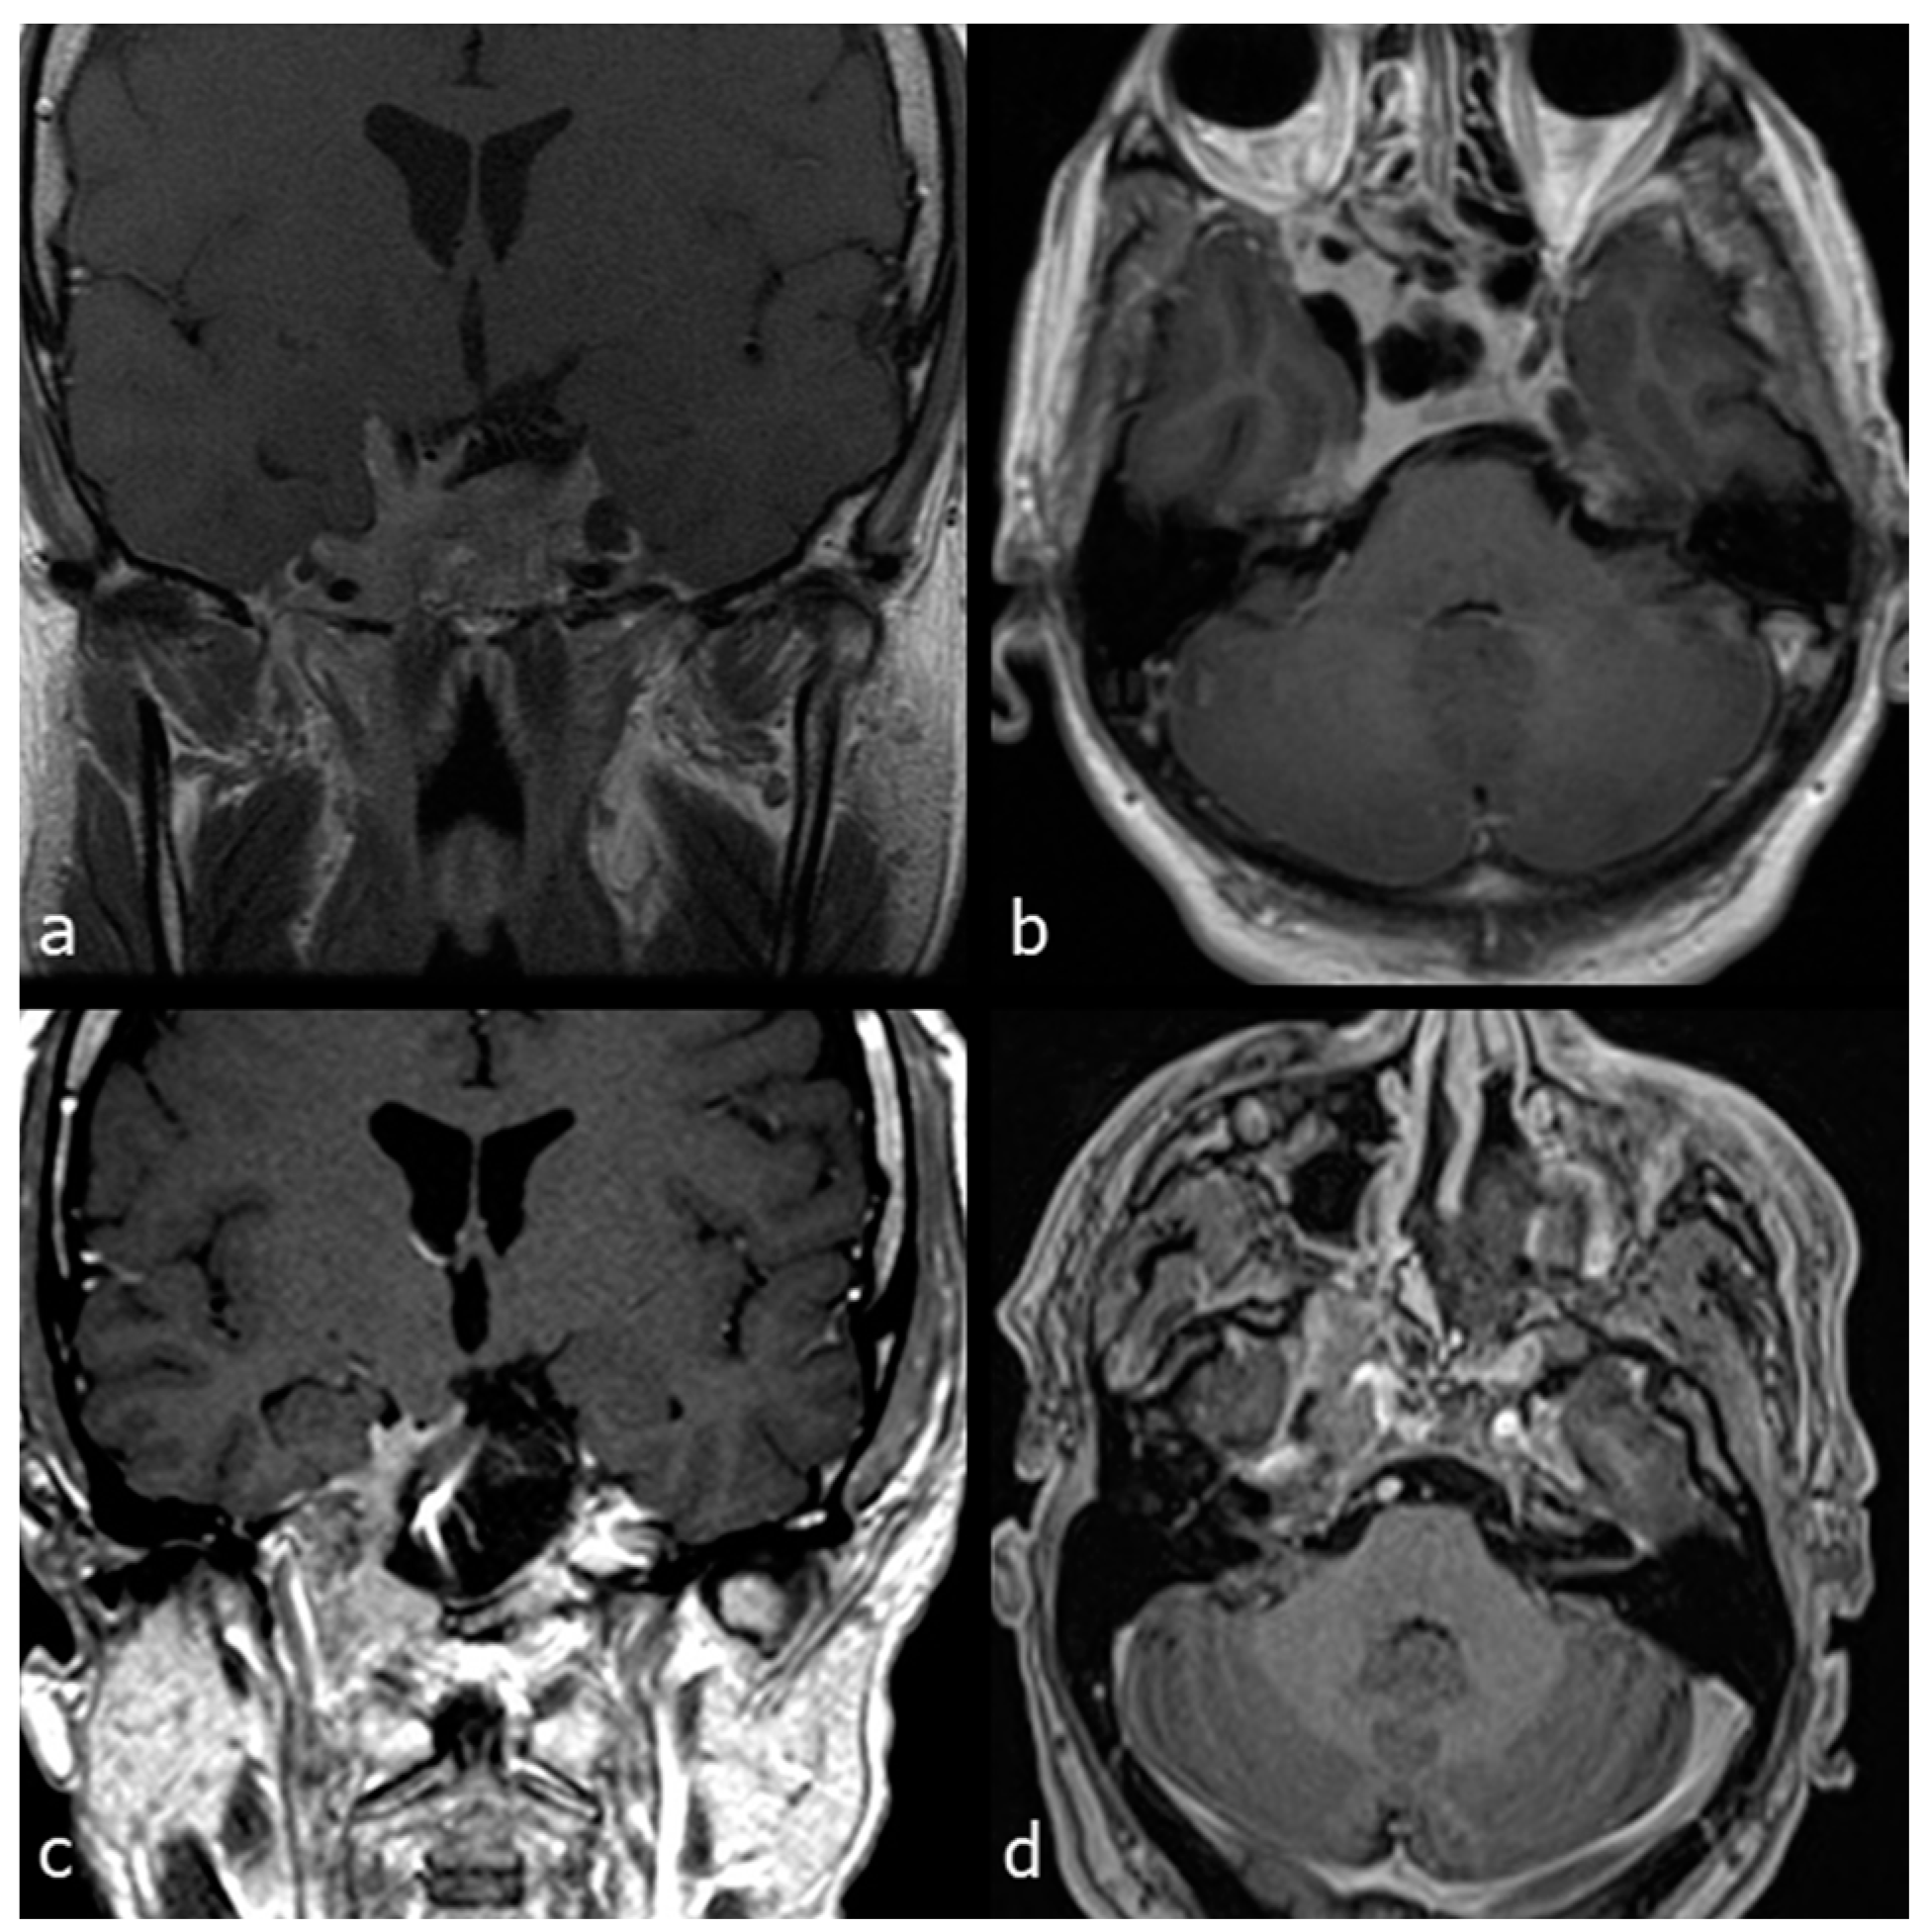

A 44-year-old woman affected by a large cranio-cervical junction chordoma subtotally resected through a retrosigmoid craniotomy 5 years before presented a slowly progressive tumour recurrence. A contrast-enhanced brain MRI showed a significant bilateral invasion of the petroclival region, with remarkable brainstem compression and displacement, and an extension towards the left parapharyngeal space. The patient presented with dysphonia and mild dysphagia. The tumour was approached through a combined EETC, left trans-pterygoid and CTM approach. The pcICA was exposed on the left side. Tumour resection was started through the endonasal corridor to remove the brainstem extradural component of the lesion. Then, the left parapharyngeal tumour portion was accessed using the endonasal corridor for endoscopic visualization and the transmaxillary route for surgical resection. A right nasoseptal flap was used for skull base reconstruction. Near total resection was obtained, as shown by the postoperative MRI (Figure 6).

Figure 6.

Case 1: preoperative and postoperative MRI scans of a large cranio-cervical junction chordoma, underwent first surgery through a retrosigmoid craniotomy, and then operated on by a combined EETC and CTM approach. (a) preoperative MRI scan, axial view. (b) preoperative MRI scan, coronal view. (c) postoperative MRI scan, axial view. (d) postoperative MRI scan, coronal view.